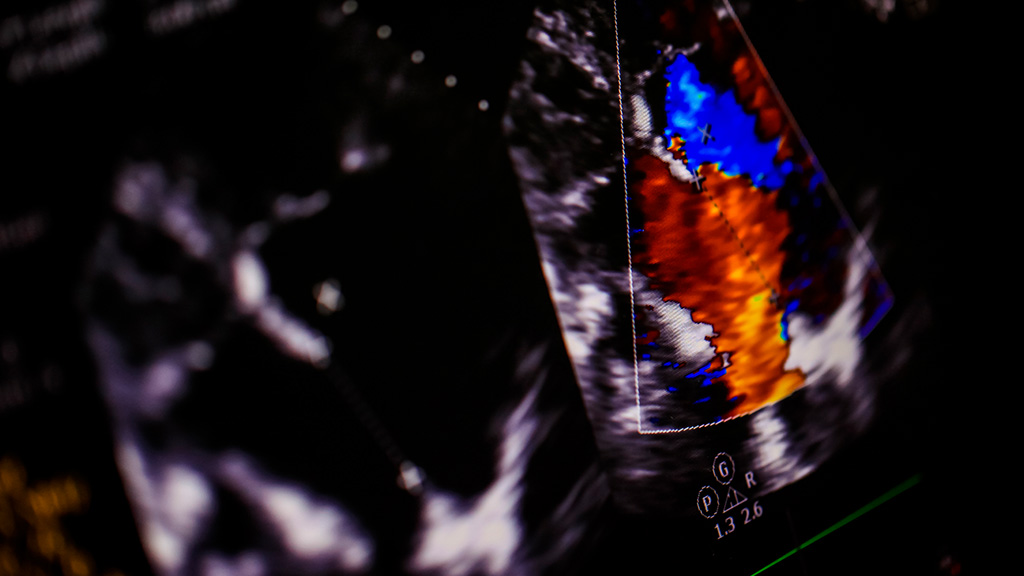

Ultrasonido Doppler Color Disfunción Erec.(S/Medi)